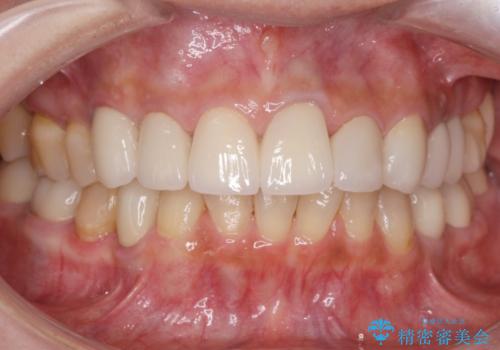

[ 審美歯科 ] ジルコニアクラウンで自然な歯に